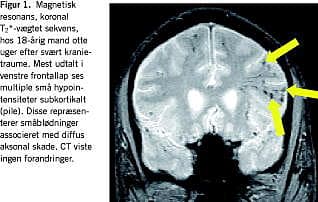

Fluid-attenuated inversion recovery (FLAIR) er en anden værdifuld MR-sekvens, som specielt muliggør visualisering af læsioner nær cerebrospinalvæsken, hvilket ellers er vanskeliggjort af det kraftige signal herfra [3]. Nonhæmoragiske DAI-læsioner kan sommetider synliggøres med denne sekvens. FLAIR er desuden velegnet til visualisering af andre traumatiske læsionstyper eksempelvis kontusioner [3] (Figur 2 ).